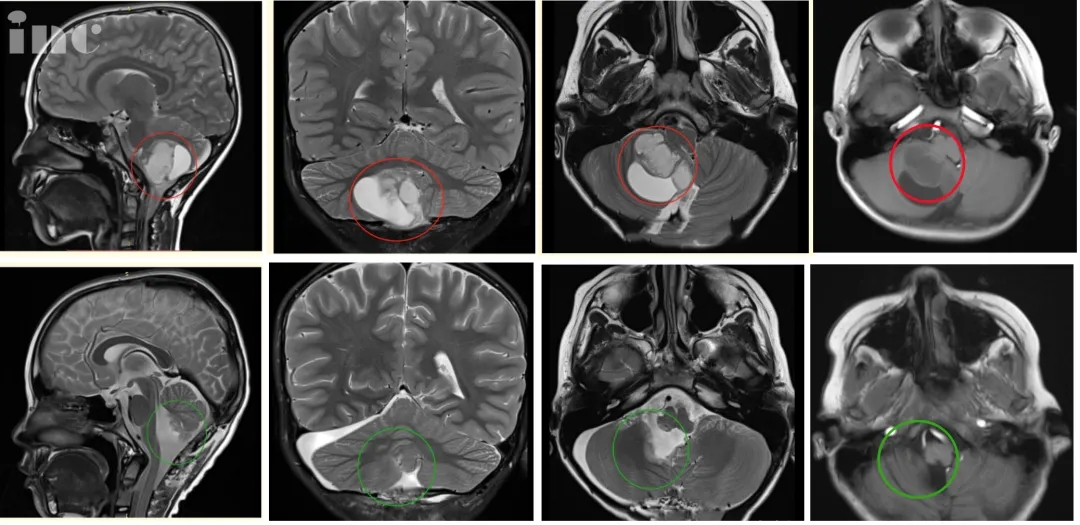

术后情况:患者在术中神经电生理检测护航下,于显微镜下全切肿瘤,术后MR复查确认了肿瘤全部切除,无残余,肿瘤囊肿部分也予以“开窗”、囊壁切除,双极电凝彻底烧灼基底,保护周边正常脑组织,脑干得到充分减压,对中脑的挤压/移位压力明显减少,小脑组织大部分复位。

术前术后影像对比:术后MR复查显示肿瘤全部切除,无残余,脑干得到充分减压,对中脑的挤压/移位压力明显减少,小脑复位。